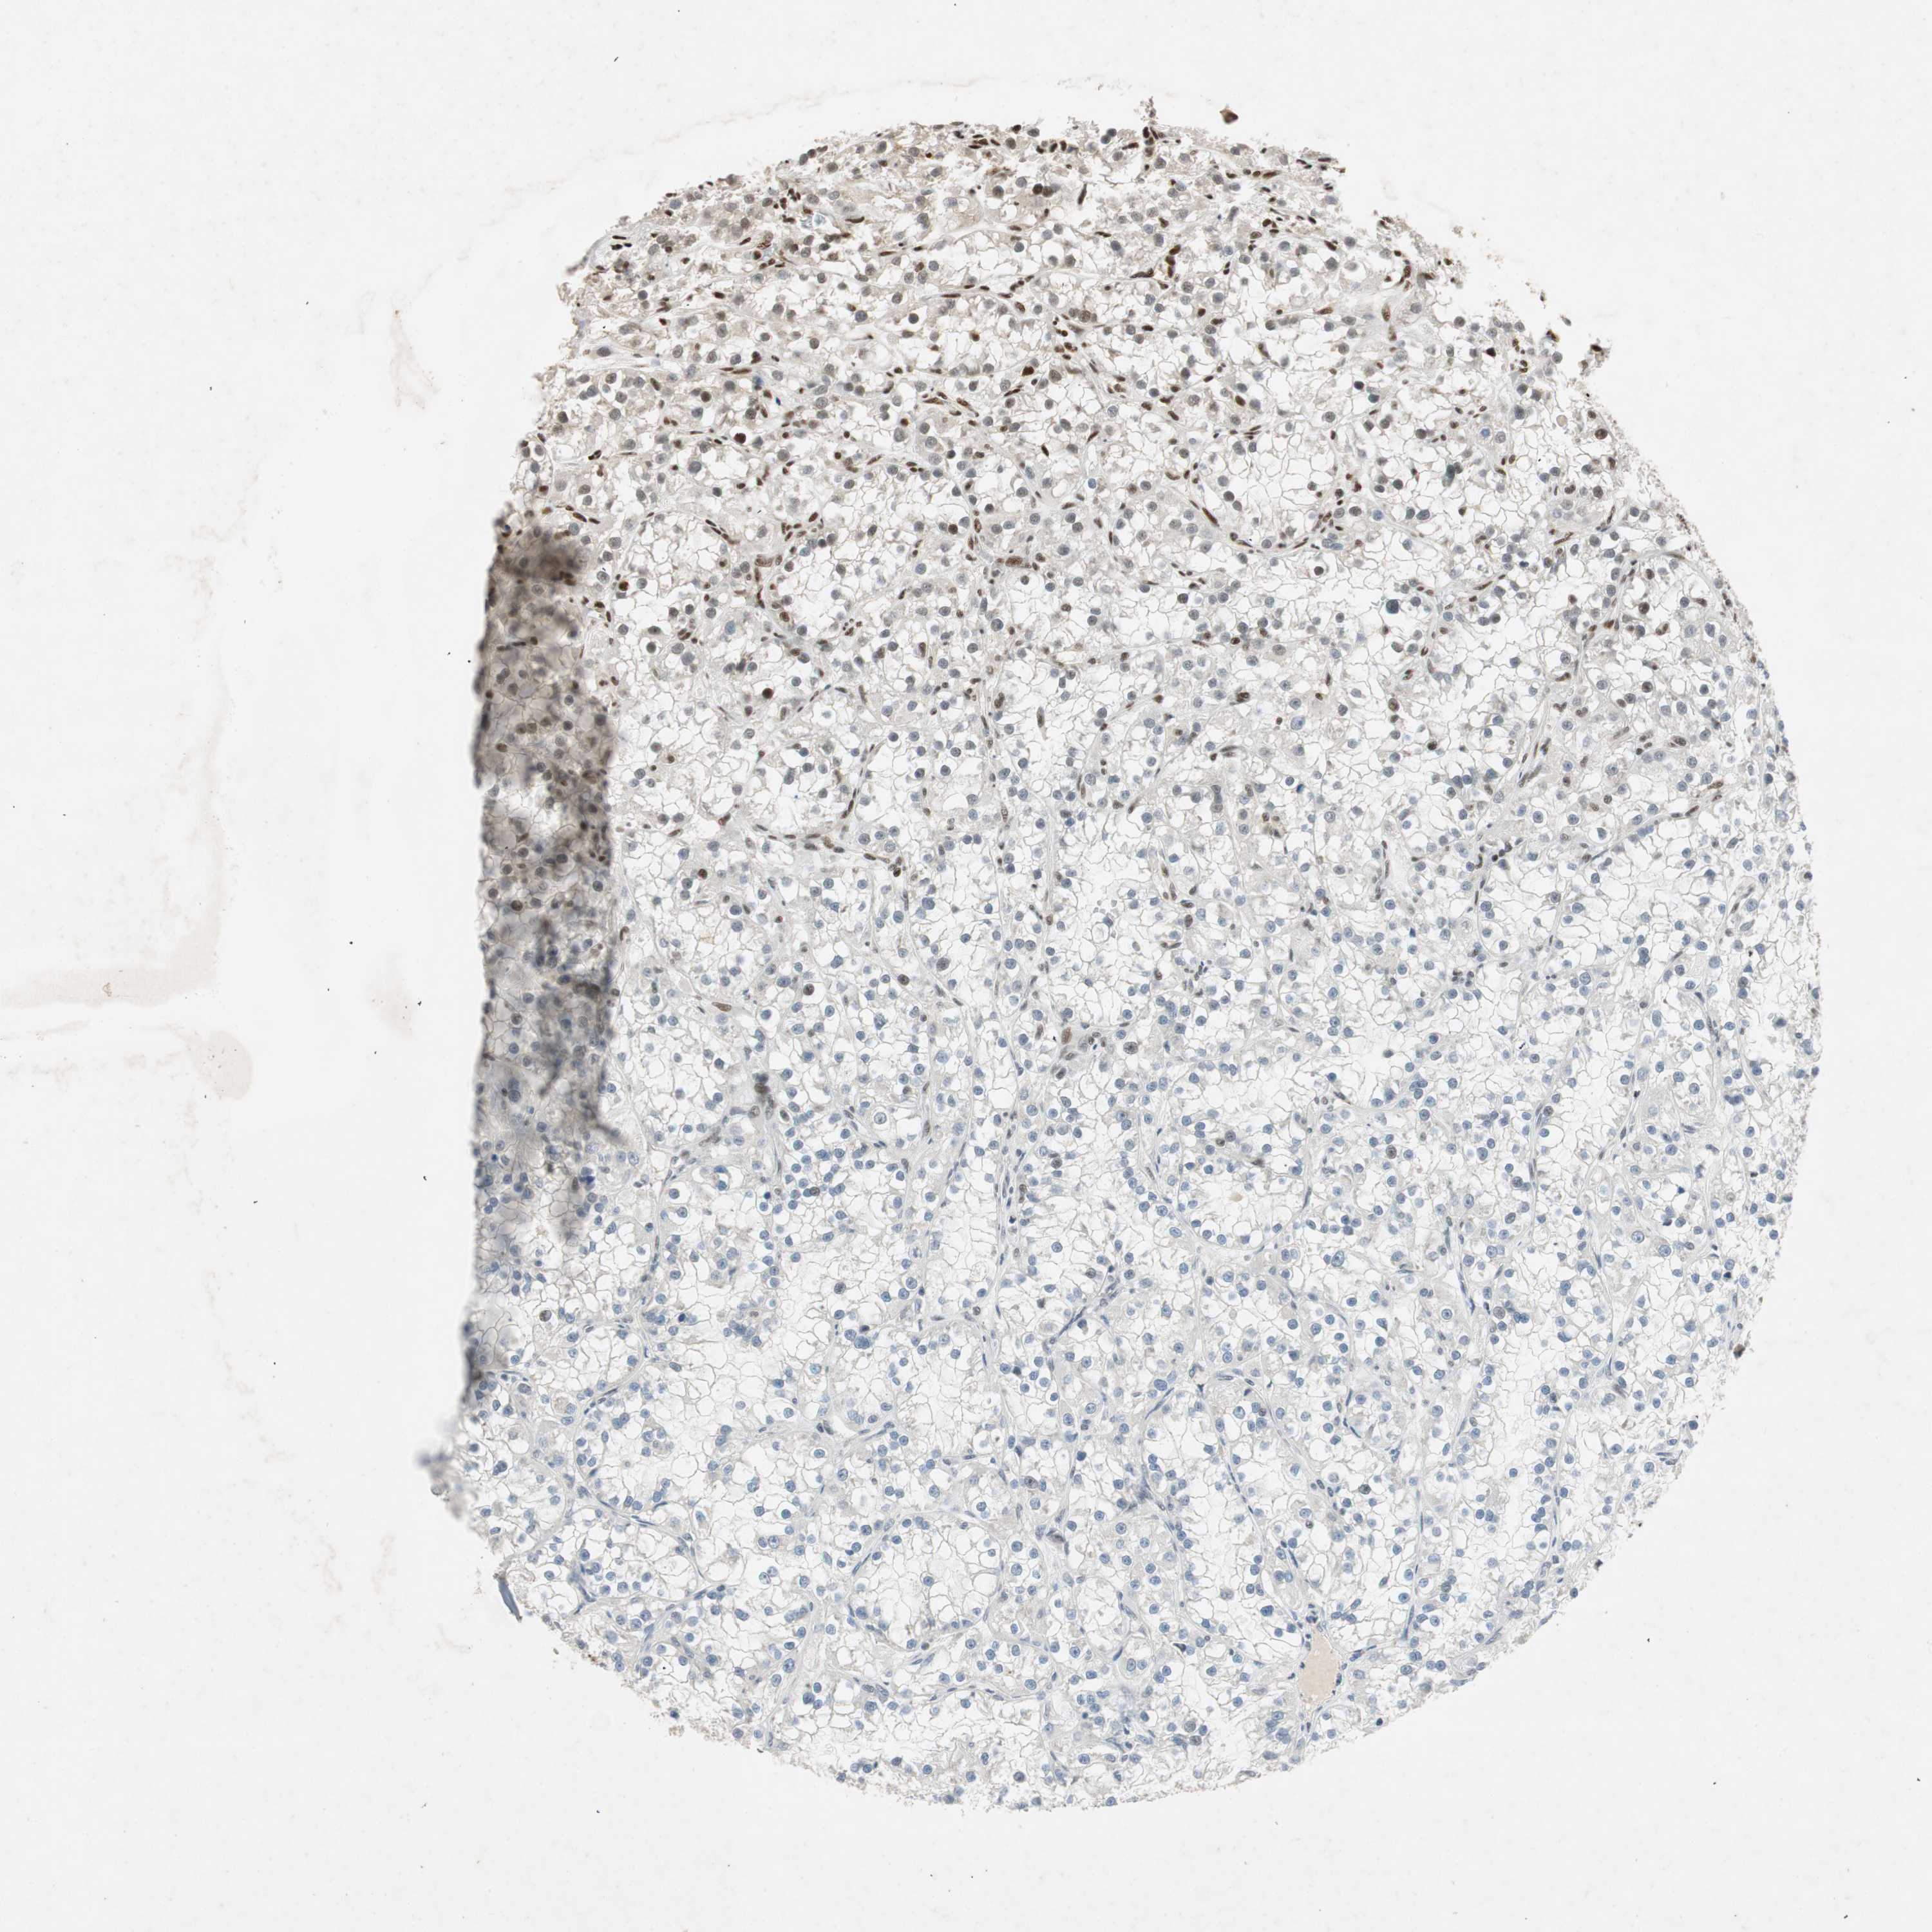

KIDNEY RENAL CLEAR CELL CARCINOMA (TCGA) - Interactive survival scatter ploti

The Survival Scatter plot shows the clinical status (i.e. dead or alive) for all individuals in the patient cohort, based on the same data that underlies the corresponding Kaplan-Meier plots. Patients that are alive at last time for follow-up are shown in blue and patients who have died during the study are shown in red.

The x-axis shows the expression levels (FPKM) of the investigated gene in the tumor tissue at the time of diagnosis. The y-axis shows the follow-up time after diagnosis (years). Both axes are complimented with kernel density curves demonstrating the data density over the axes. The top density plot shows the expression levels (FPKM) distribution among dead (red) and alive patients (blue). The right density plot shows the data density of the survived years of dead patients with high and low expression levels respectively, stratified using the cutoff indicated by the vertical dashed line through the Survival Scatter plot. This cutoff is automatically defined based on the FPKM cutoff that minimizes the p-score. The cutoff can be changed by dragging the vertical line or by entering a cutoff value in the square labeled "Current cut-off".

Under the Survival Scatter plot the p-score landscape (black curve; left axis) is shown together with dead median separation (red curve; right axis). Dead median separation is the difference in median mRNA expression between patients who have died with high and low expression, respectively. It is calculated as follows: median FPKM expression of dead patients with high expression - median FPKM expression of dead patients with low expression. This is intended to aid the user in visually exploring custom cutoffs and the associated p-scores and dead median separation.

Individual patient data is displayed and can be filtered by clicking on one or more of the category buttons on the top of the page. Categories describing expression level and patient information include: high, low, alive, dead, female, male and tumor stages. The scale of the x-axis can be toggled between linear and log-scale by clicking on the "x log" button. Mouse-over function shows TCGA ID, patient information and mRNA expression (FPKM) for each patient.

& Survival analysisi

Kaplan-Meier plots summarize results from analysis of correlation between mRNA expression level and patient survival. Patients were divided based on level of expression into one of the two groups "low" (under cut off) or "high" (over cut off). X-axis shows time for survival (years) and y-axis shows the probability of survival, where 1.0 corresponds to 100 percent.

NCBP3 is not prognostic in Kidney Renal Clear Cell Carcinoma (TCGA)

Best expression cut offi

Based on the FPKM value of each gene, patients were classified into two groups and association between prognosis (survival) and gene expression (FPKM) was examined. The best expression cut-off refers the FPKM value that yields maximal difference with regard to survival between the two groups at the lowest log-rank P-value. Best expression cut-off was selected based on survival analysis .

When clicking on this number, the vertical dashed line indicating cut-off, the interactive survival plot, and the Kaplan-Meier curve will be adjusted to show results based on the best expression cut-off.

: 4.43

P scorei

Log-rank P value for Kaplan-Meier plot showing results from analysis of correlation between mRNA expression level and patient survival.

N/A

TCGA RNA samplesi

RNA-seq data is reported as average FPKM (number Fragments Per Kilobase of exon per Million reads), generated by the The Cancer Genome Atlas (TCGA) .

Normal distribution across the dataset is visualized with box plots, shown as median and 25th and 75th percentiles. Points are displayed as outliers if they are above or below 1.5 times the interquartile range. FPKM values of the individual samples are presented next to the box plot.

Average pTPM 5.6

Number of samples 521